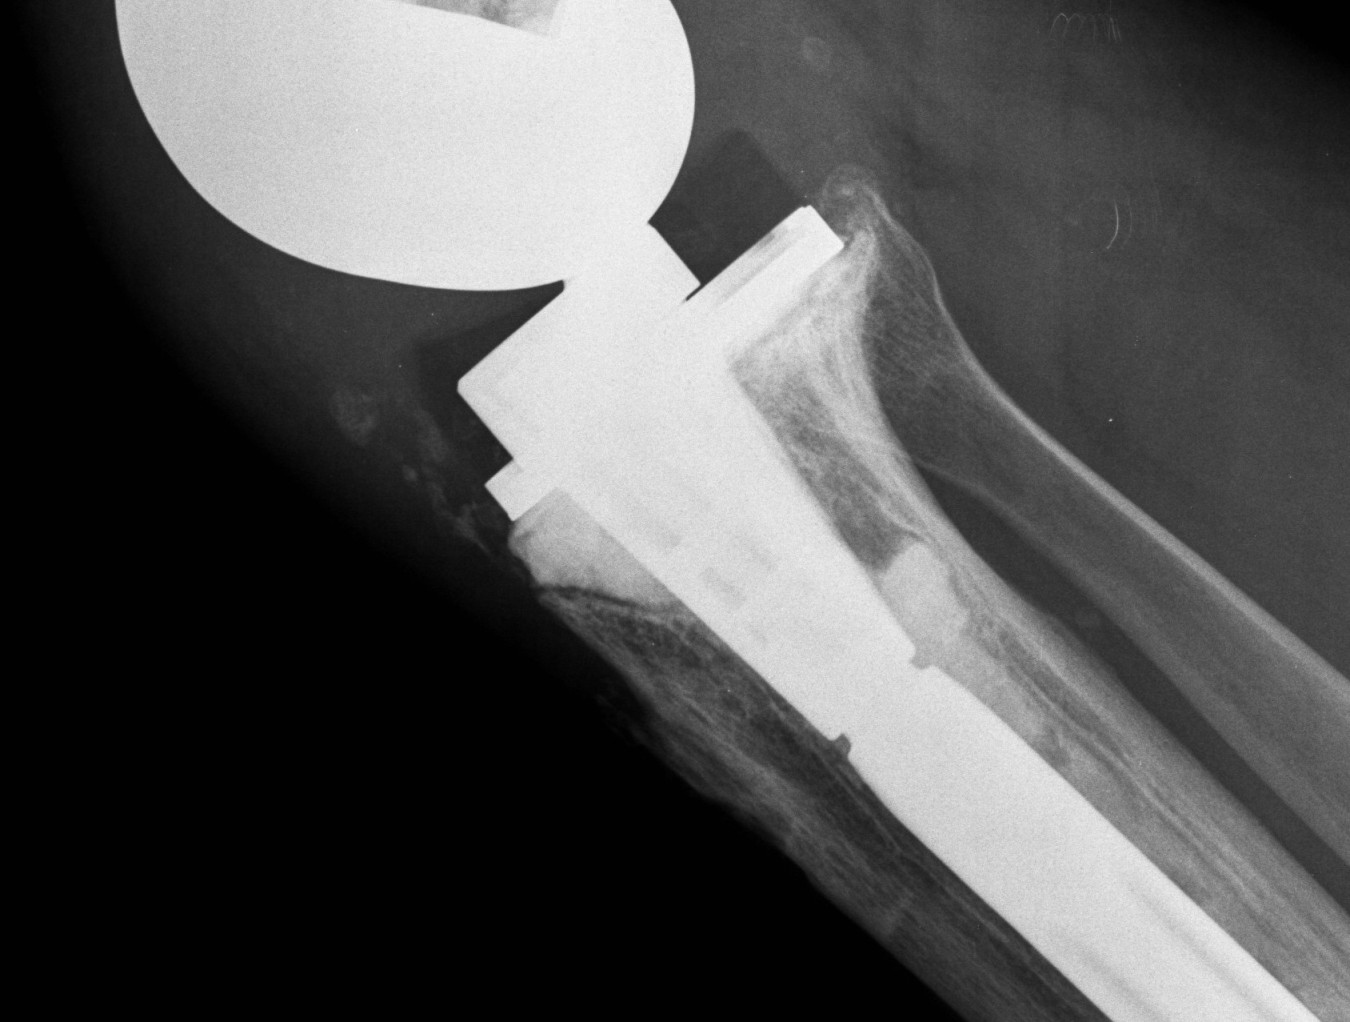

A. Bulk structural allograft

- femoral head

Engh et al JBJS Am 2007

- bulk structure allograft in the tibia in 46 patients followed for 8 years

- 2 deep infections

- average knee society scores 84

- no graft collapse or loosening